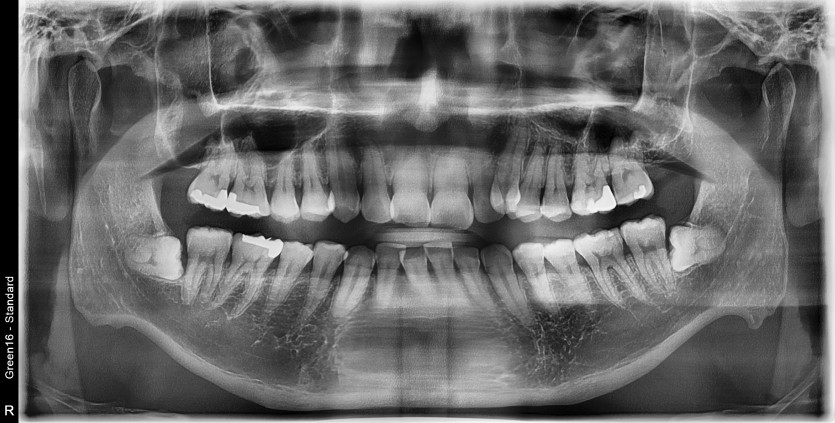

#38 사랑니 발치

구강 외과 전문의가 당일 발치했습니다.